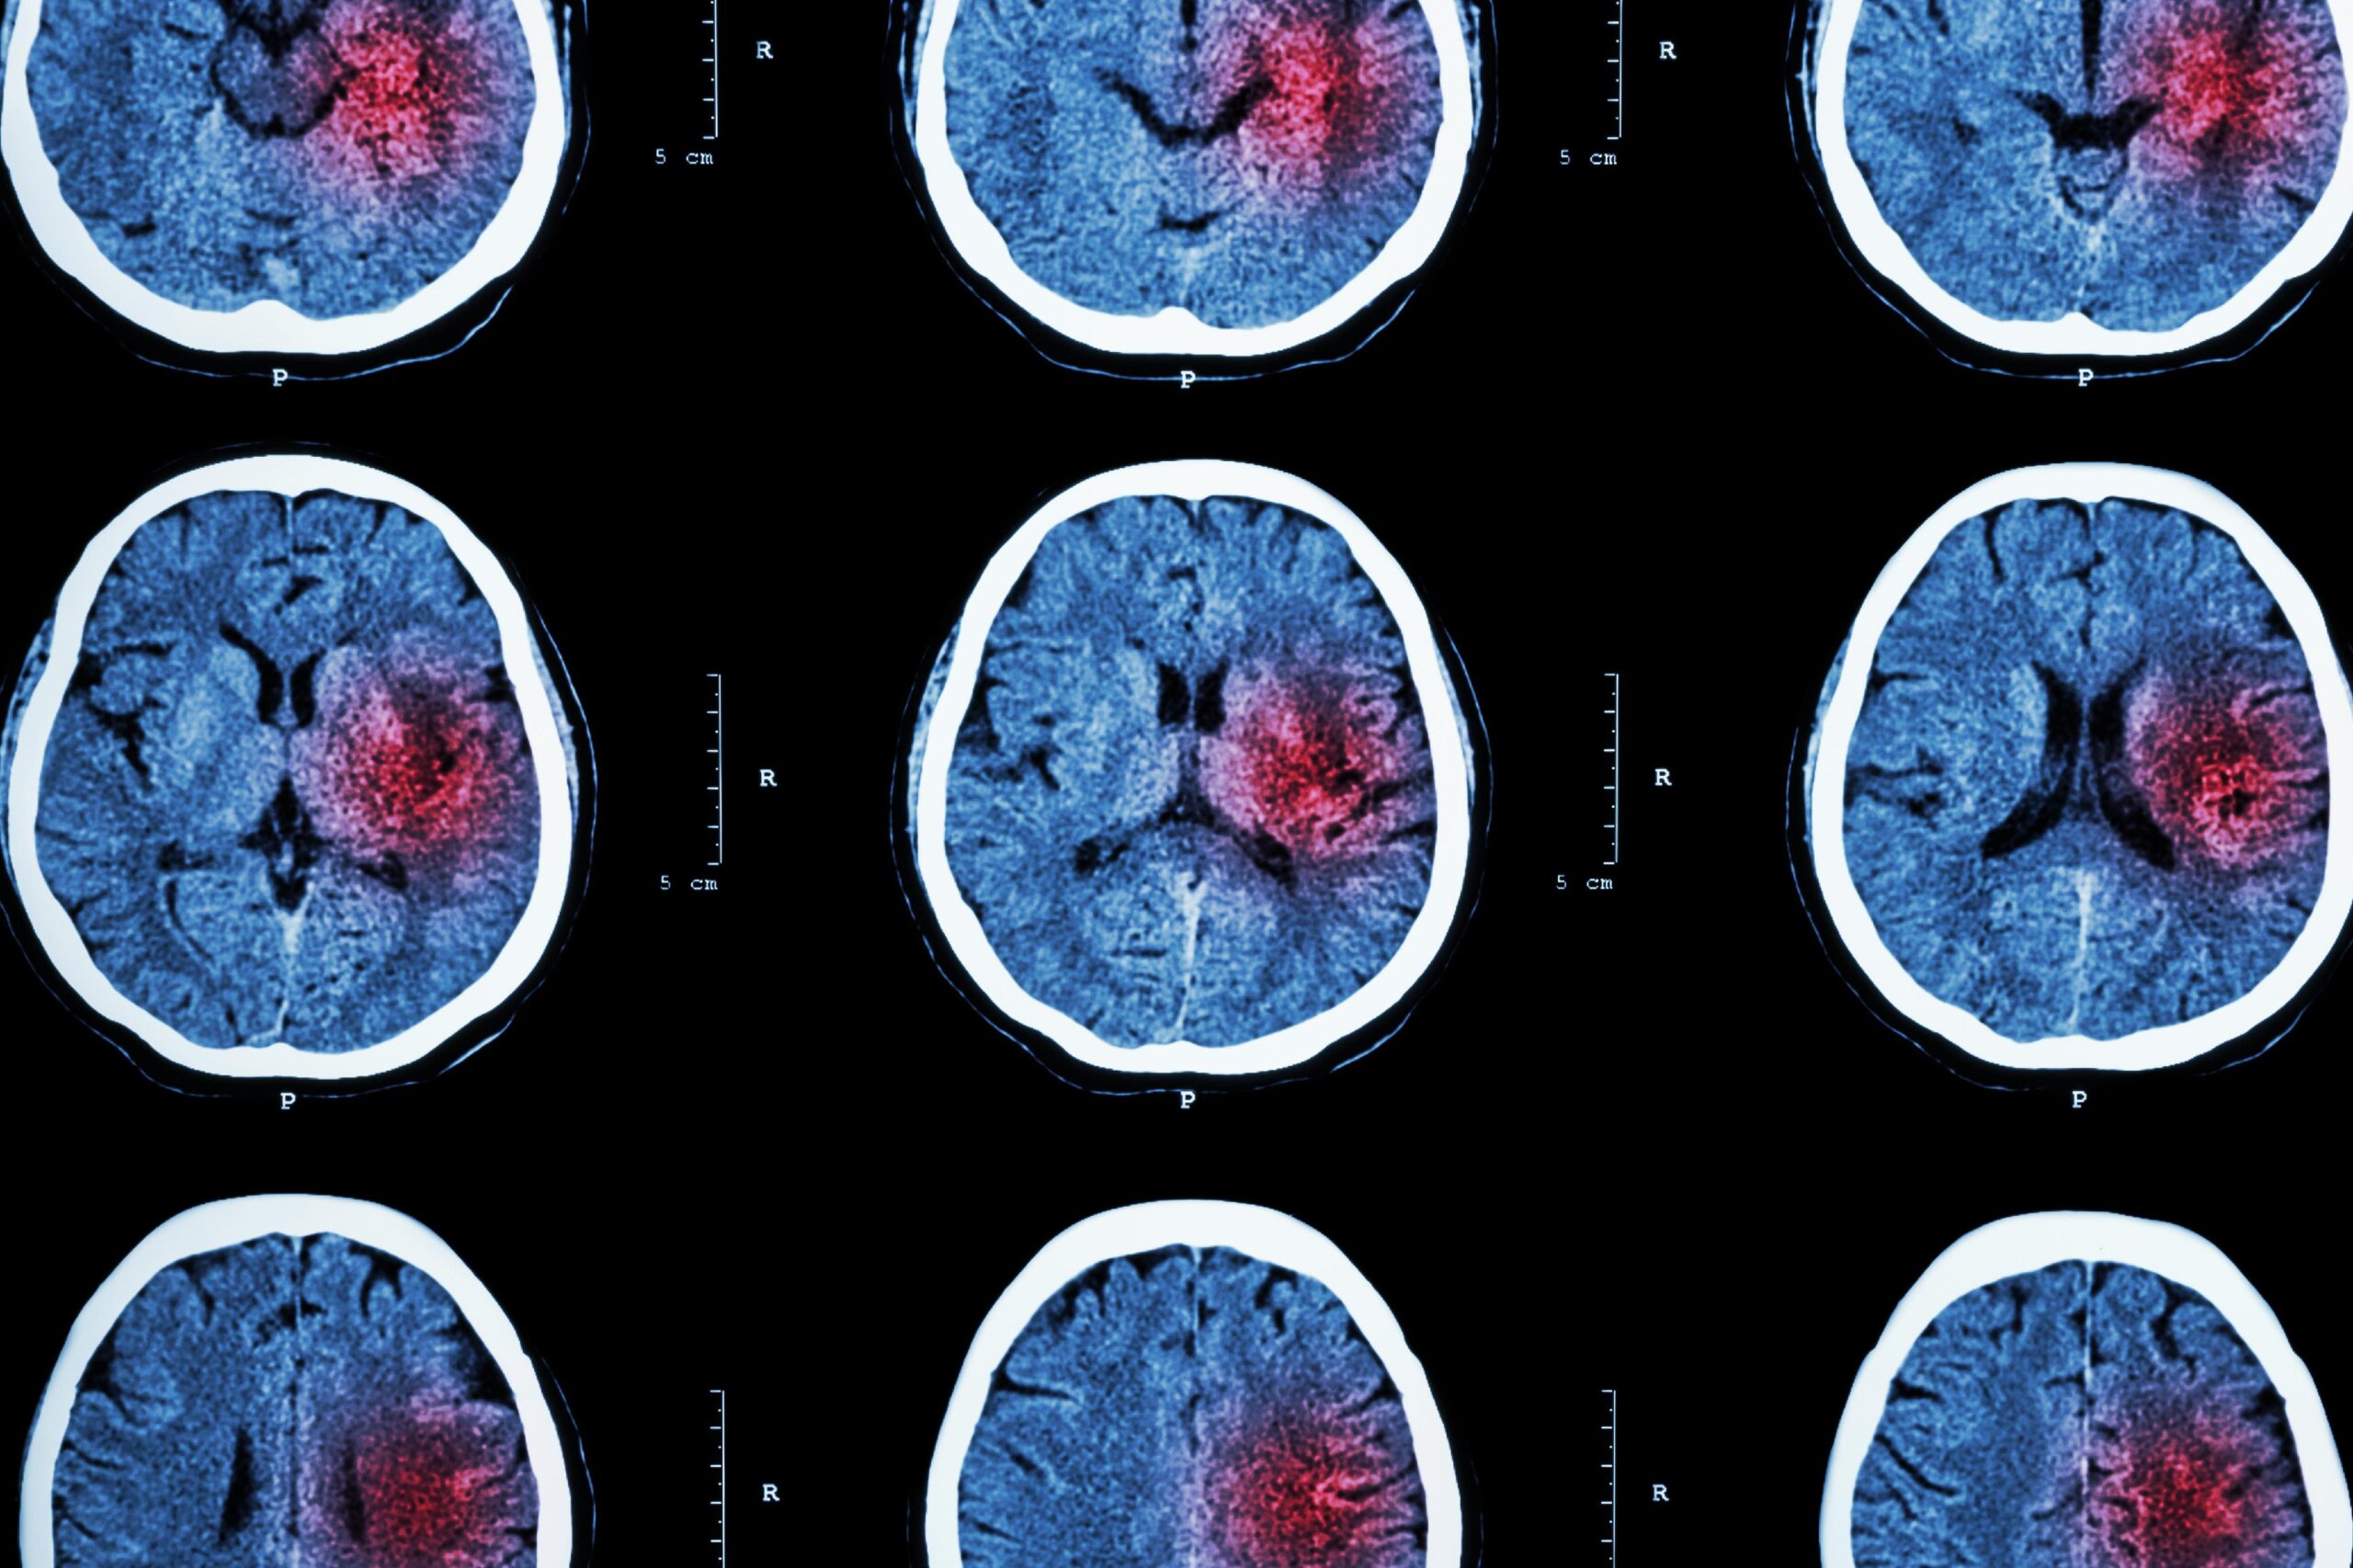

Os resultados mostraram melhorias significativas: nos animais de teste, as funções neurológicas melhoraram em 25%, a integridade esquelética foi preservada e o suprimento sanguíneo para o córtex cerebral aumentou consideravelmente.